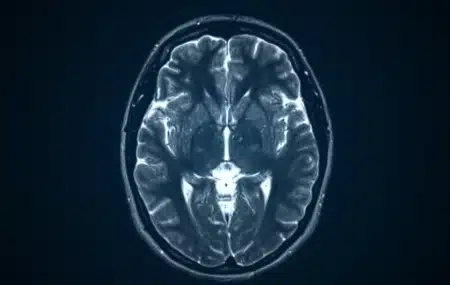

A look at how regenerative medicine offers new hope for lasting seizure relief for drug-resistant epilepsy.